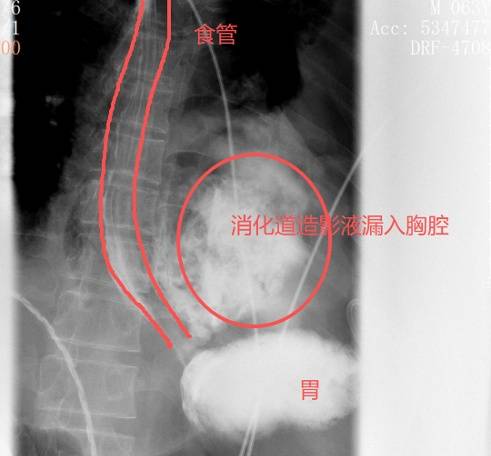

转(zhuan)院时,患者病因成谜(mi)。在晨会接班时,胸外科主任刘继(ji)先灵(ling)敏地捕捉到一个关键细节,他(ta)多(duo)问了一句(ju):“这个病人,发病前有没(mei)有吐逆?”“有!吃完包子(zi)之(zhi)后吐了两次,吐完就最先痛了。”在获得确(que)定答复后,刘主任立即警觉,判(pan)断这多(duo)是一种极其(qi)凶险的疾病——“自发性(xing)食(shi)管破裂”(Boerhaave综合征),并紧急支配(pei)了口服钡餐(can)搜检。

效果证明了他(ta)的判(pan)断:

钡剂从食(shi)道下段的裂口处

大批漏入了左边胸腔

红圈区域是食(shi)品(pin)残渣、消化液破入食(shi)管